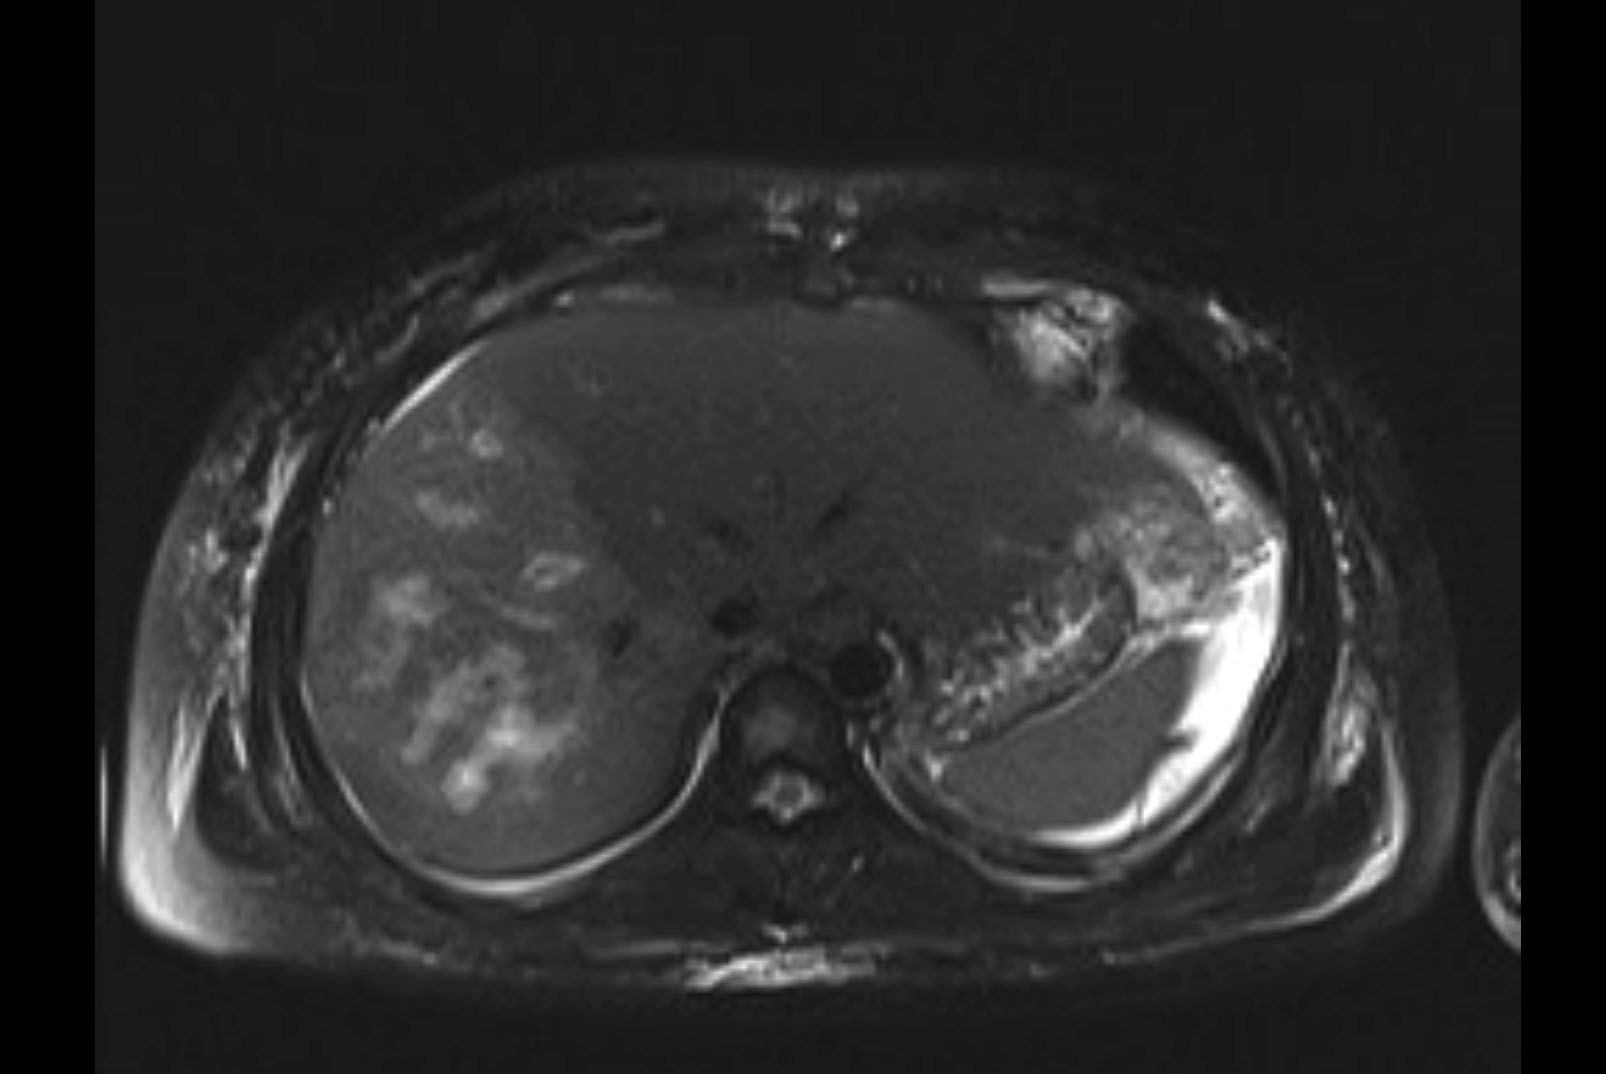

MRI T2

Imaging analysis

Based on initial findings, which issue(s) would you be most concerned about?